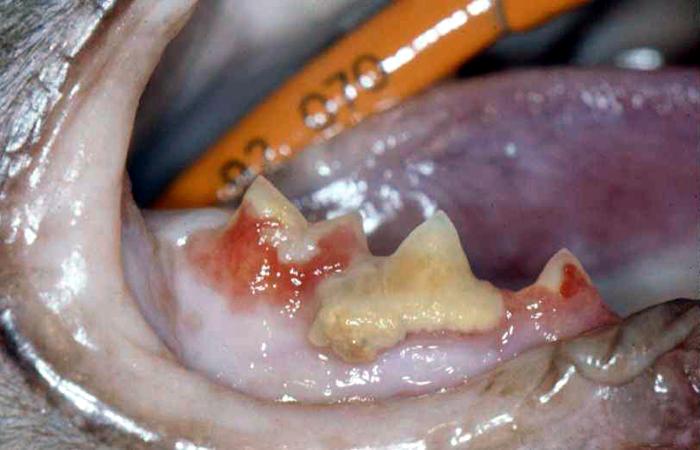

- Synlige symptomer på TR ses som regel ved tandkødskanten, hvor tandkødet er blevet mere rødt og evt. er vokset lidt op over kanten.

Finder man mere end en tand med synlige TR vil der være risiko for, at flere tænder er angrebet.

Billeder af katte med Tooth Resorption (TR/FORL):